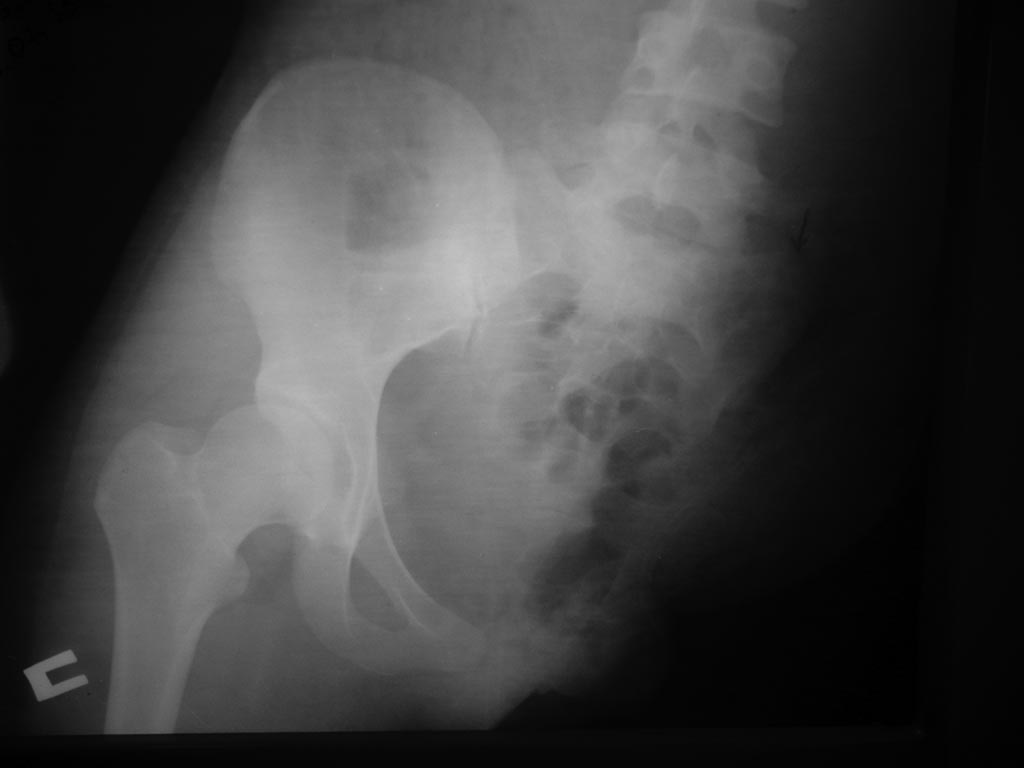

Уважаемые коллеги, возможно ли протезирование при травматическом отрыве левой половины таза и нижней конечности.

Больная К. 20 лет

Ds: Тяжёлая сочетанная травма в ДТП. Травматический отрыв левой половины таза и левой нижней конечности. Обширная размозжённая рана передней брюшной стенки слева, таза и ягодичной области слева с обширным дефектом мышц передней брюшной стенки.

Уважаемые коллеги, возможно ли в дальнейшем протезирование данной больной и где?